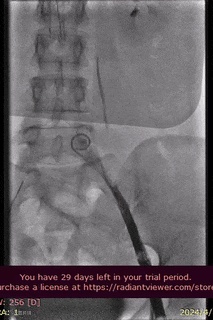

手术过程